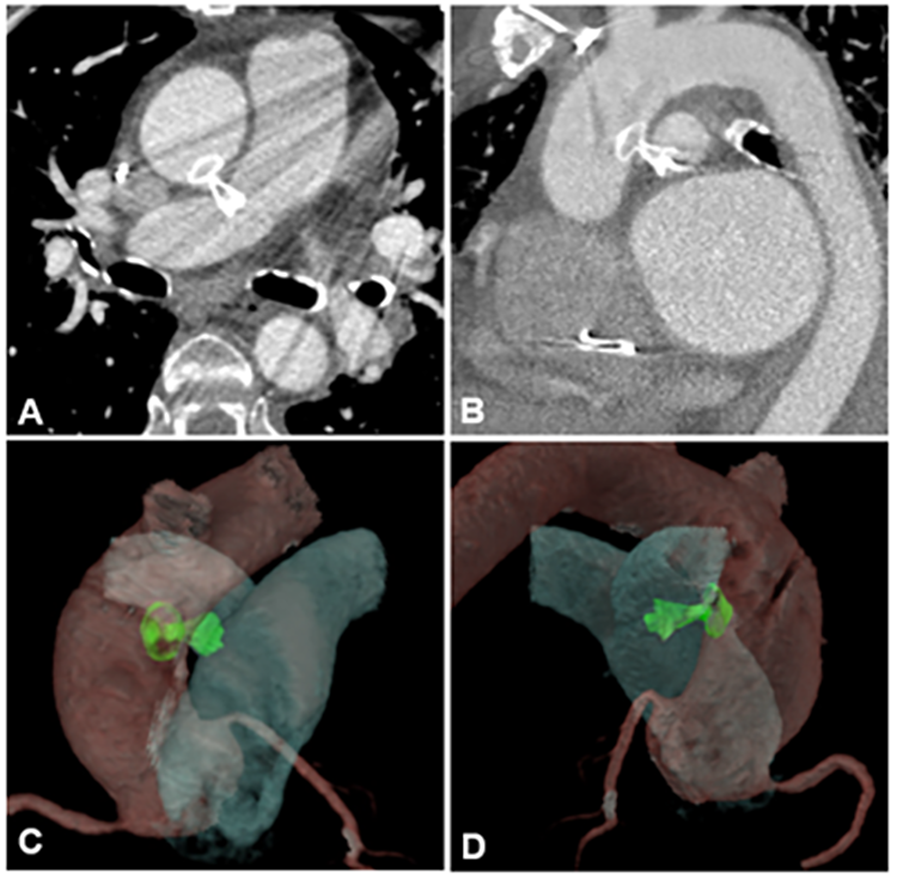

During the 9-month follow-up period, the patient demonstrated significant clinical improvement with resolution of symptoms. A follow-up CTA of the aortic and pulmonary vessels confirmed the correct position of the device (Figures 3A–D), with a slight protrusion into the lumen of the proximal right pulmonary artery. TEE showed no evidence of pulmonary artery flow obstruction, pressure gradients, or hemodynamic compromise.

Figure 3

Images of aortic and pulmonary vessels angiotomography (A,B) performed after aortopulmonary fistula correction procedure, during the follow-up and its 3D reconstruction (C,D).